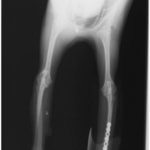

トイプードル 右遠位橈尺骨短斜骨折のALPSによる内固定

LCPは、スクリュー(ネジ)とプレート(金属の板)をロックする特殊な構造により骨折部位を固定する新しい世代のプレートシステムです。ひとつのホールでロッキングスクリューとスタンダードスクリューの使用を選択できるユニークな構造をしているため、骨折断端間の圧迫を目的とした従来型プレート固定法に加え、高い角度安定性を有するロッキングスクリューを用いた固定法の選択が可能です。従来のプレートシステムでは困難だった部分の骨折や癒合不全の症例に高い治療効果をもたらします。

当院ではAdvanced Locking plate system(ALPS)と、Locking compression plate system(LCPS)という骨接合法で骨折症例の治療を行っています。